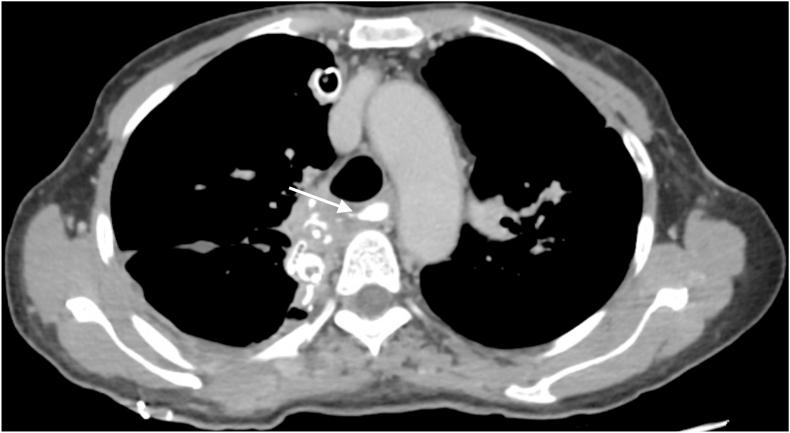

We present the case of a 58-year-old woman who developed dysphagia, regurgitation, and substantial weight loss (11 kg) over a span of 1 year. Symptomatic achalasia with megaesophagus was diagnosed following chest and abdominal computed tomography (CT) with contrast and transit RX with gastrografin and esophageal manometry. The patient refuse all minimally endoscopic treatments and opted straightly for the treatment with esophagectomy sec. Ivor-Lewis. At the 6-month follow-up, the patient appeared in excellent general clinical condition and oral gastrografin radiography (OGR) showed good channeling.

我们报告一例58岁女性患者,在1年时间内出现吞咽困难、反流及体重显著减轻(11千克)。经胸部和腹部增强计算机断层扫描(CT)、泛影葡胺食管造影及食管测压后,诊断为有症状的贲门失弛缓症合并巨食管。患者拒绝所有微创内镜治疗,直接选择了艾弗·刘易斯(Ivor-Lewis)式食管切除术。在6个月的随访中,患者总体临床状况良好,口服泛影葡胺造影(OGR)显示食管通道良好。